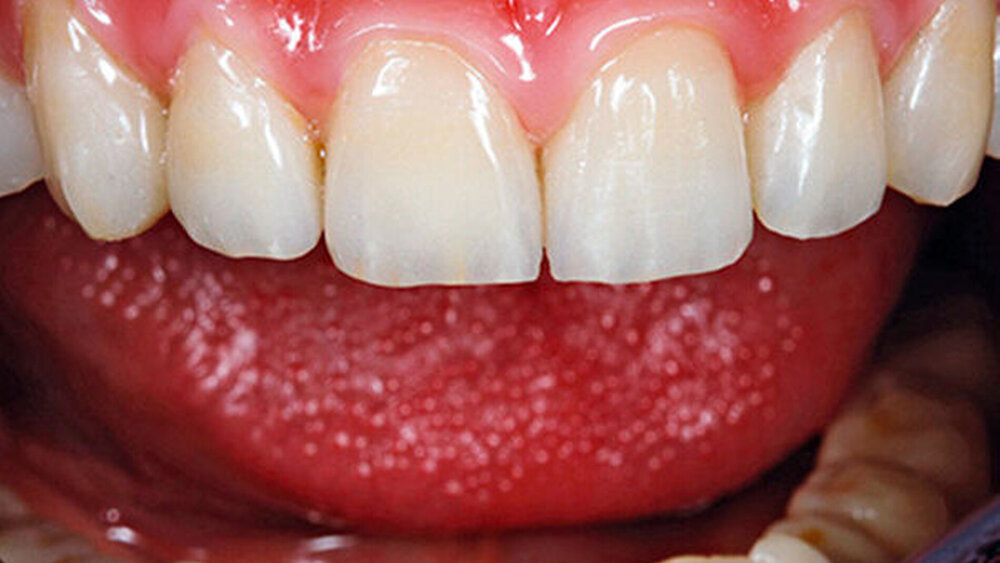

Eine 67 Jahre alte Patientin stellte sich mit dem Wunsch einer Oberkiefersanierung in unserer Praxis vor. Ihre Restzähne waren aufgrund von Parodontitis und funktioneller Überlastung nicht mehr erhaltungswürdig. Wir ließen sie bis kurz vor der definitiven Versorgung als strategische Pfeilerzähne für die Interimsprothese in situ.

Das hat nichts mit den unterschiedlichen Protokollen zu tun. Der Übergang zwischen Restauration und dem Abutment darf nicht sichtbar sein, egal bei welchem Protokoll. Entweder werden die Implantate deshalb tiefer gesetzt oder der Knochen wird abgetragen. Unproblematischer ist das im Unterkiefer, die Lippe und die Lippenbänder verdecken viel. Wir implantieren – wann immer das geht – erst in der 3er-, 4er-, 5er-Position, nicht direkt in der Front.